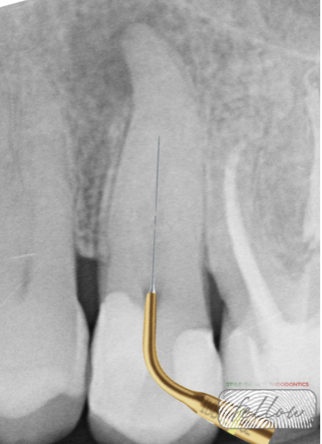

Fig. 4

Root canal shaping was performed using a combined rotary system to achieve optimal shaping and apical enlargement while preserving the original canal anatomy: Mtwo rotary files and ProTaper Gold finishing files.

- Mtwo Purple 10/.04 – initial shaping of coronal and middle thirds

- Mtwo White 10/.05 – shaping of coronal and middle thirds

- ProTaper Gold F1 – apical finishing

- ProTaper Gold F2 – final apical enlargement and continuous tapering